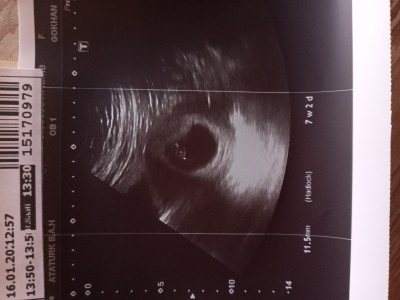

image

kuzenimin ultrason resmi bu canlar

Sizinkilerin nasıl

Erkek bebek olabilir tahmin ediyorum sadece çünkü benimki daha yuvarlaktı ve kız bebekti

Benimkilerde öyleydi

Sağol kuzum :))